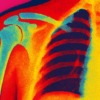

スポンサーリンク 石灰沈着性腱板炎の闘病記 全7記事まとめ2025年9月13日 石灰沈着性腱板炎になった話①人生で二度目の石灰沈着性腱板炎です。この症状の始まり、どんな凄まじい痛みなのか、どうやって過ごし ... https://okeiko.blog/life/shoulder_pain_day1/ 石灰沈着性腱板炎になった話②石灰沈着性腱板炎になって2~3日目。痛みは本格的になり、夜は激痛で眠れず座ったままで一夜を明かし ... https://okeiko.blog/life/shoulder_pain_day2-3/ 石灰沈着性腱板炎になった話③石灰沈着性腱板炎の激痛に痛み止めを飲んで、テレビを観て気を逸らせて一日過ごします。でも夜の痛みに ... https://okeiko.blog/life/shoulder_pain_day3-4/ 石灰沈着性腱板炎になった話④石灰沈着性腱板炎の痛みも、だんだんと回復してきています。痛みを我慢することは意味が無いと気づき、 ... https://okeiko.blog/life/shoulder_pain_day5-6/ 石灰沈着性腱板炎になった話⑤石灰沈着性腱板炎になって6~7日目です。痛みの変化についてや痛み止めの利用についてなどリアルに語り ... https://okeiko.blog/life/shoulder_pain_day6-7/ 石灰沈着性腱板炎になった話⑥石灰沈着性腱板炎になり7~8日目です。激痛を伴う辛い症状はどのように回復してきたのか、今どのような ... https://okeiko.blog/life/shoulder_pain_day7-8/ 石灰沈着性腱板炎になった話【まとめ】石灰沈着性腱板炎になり、どうにか治した私の今までをまとめ記事にしました。結局どうしたらいいのか、 ... https://okeiko.blog/life/shoulder_pain_summary/ スポンサーリンク 美容と健康石灰沈着性腱板炎Posted by Keiko